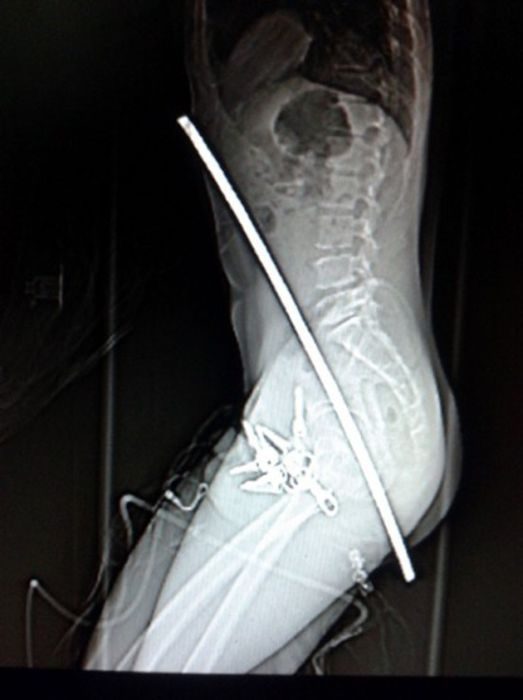

Этот парень слишком буквально понял смысл фразы — «ты должен оставить прошлое позади»